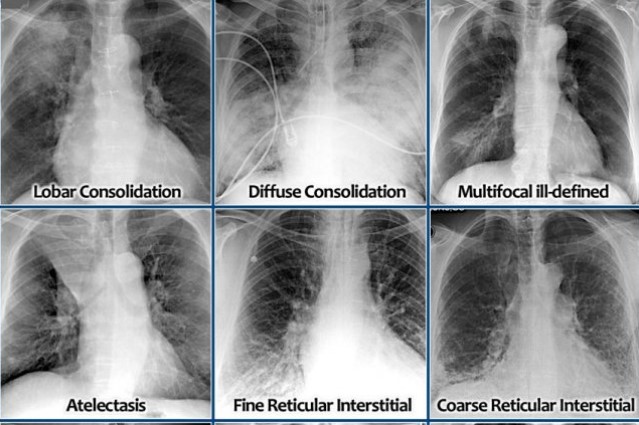

Identifying Injuries and Abnormalities:

Radiologists examine X-ray and CT scan images to identify signs of injuries, such as fractures, dislocations, or soft tissue damage. They also look for abnormalities, such as masses, tumors, fluid collections, or signs of infection. By carefully analyzing the images, radiologists can determine the location, size, and characteristics of the abnormalities and provide valuable insights into the underlying conditions.